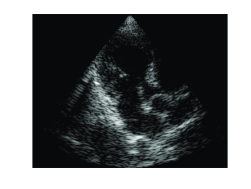

Applying an IDFT on {ck}k=1Nsuperscriptsubscriptsubscript𝑐𝑘𝑘1𝑁\{c_{k}\}_{k=1}^{N}, we obtain the beamformed signal. We can now proceed to standard image generation steps which include log-compression and interpolation. To demonstrate the equivalence of beamforming in time and frequency, we applied both methods on in vivo cardiac data obtained as explained in Section 2, yielding the images shown in Fig. 2. As can be seen, both images are identical.

Refer to caption

(a)

(b)

Fig. 2: Cardiac images constructed with different beamforming techniques. (a) Time domain beamforming. (b) Frequency domain beamforming.